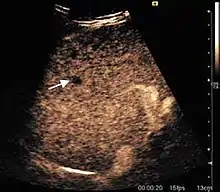

The ultrasound appearance is a well defined lesion, with very thin, almost unapparent walls, without circulatory signal at Doppler or CEUS investigation. The content is transonic suggesting fluid composition. The presence of membranes, abundant sediment or cysts inside is suggestive for parasitic, hydatid nature. Posterior from the lesion the acoustic enhancement phenomenon is seen, which strengthens the suspicion of fluid mass. They typically displace normal liver vessels but no vascular or biliary invasion occurs.

Liver cyst

Hydatid liver cyst. Diagnostic criteria are the presence of membranes and sediment inside.